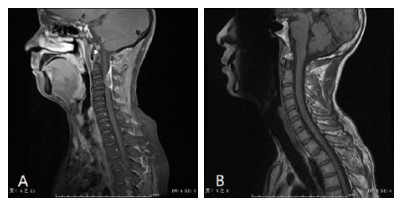

疗效评价:7例未手术患者中,除1例放弃治疗外(死亡),保守治疗2周后脊髓功能评估D级3例,E级3例。手术患者术后两周评估A级5例,C级5例,D级8例,E级4例。除1例死亡患者外,本组28例患者随访时间3~62个月,(48.7±23.1)个月。随访未手术6例患者,预后良好(评估为E级),症状完全消失,影像学检查未见复发。22例手术患者中,10例入院为A级患者中,6例恢复良好(D/E级),4例预后不佳生活不能自理(A级3例,C级1例);7例术前为C级患者随访中,基本恢复日常生活(D级2例,E级5例);而5例术前D级患者预后亦良好,随访肢体活动能力全部恢复(E级)。见表 1,图 1。

| A:矢状位提示硬膜外占位性病变,同水平脊髓受压明显;B:术后复查见血肿清除彻底,脊髓形态恢复 图 1 典型C2节段硬膜外血肿术前术后MRI影像资料 Fig 1 MRI images of typical C2 epidural hematoma before and after surgey |